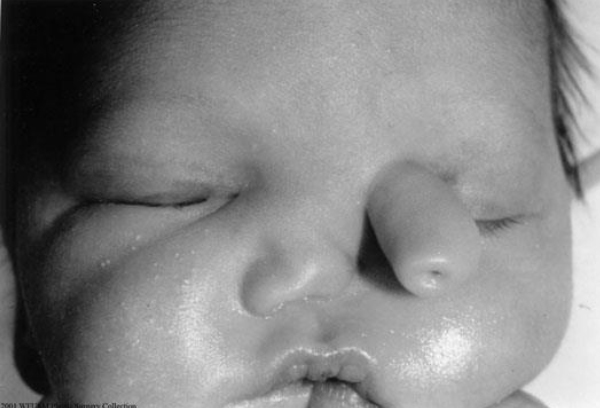

The patient shown in the photograph is most likely to have which of the following comorbidities?

The correct response is Option C.

The patient pictured has a rare craniofacial (Tessier No. 4) cleft. Rare craniofacial clefts are characterized by variable soft-tissue and bony involvement. This patient has a cleft lip that begins lateral to the philtral column and courses laterally to the alar margin. Additionally, this patient has soft-tissue deficiency of the left medial malar region, as well as medial lower lid malposition and medial canthal dystopia. Of all of the options given, these findings suggest an increased risk for nasolacrimal duct abnormalities or inferior canalicular system malposition. Velopharyngeal dysfunction is common in patients with cleft lip and palate. Anosmia can be present in midline craniofacial anomalies, such as craniofrontonasal dysplasia. Rare craniofacial (Tessier No. 4) clefts are not associated with sensorineural hearing loss or craniosynostosis.